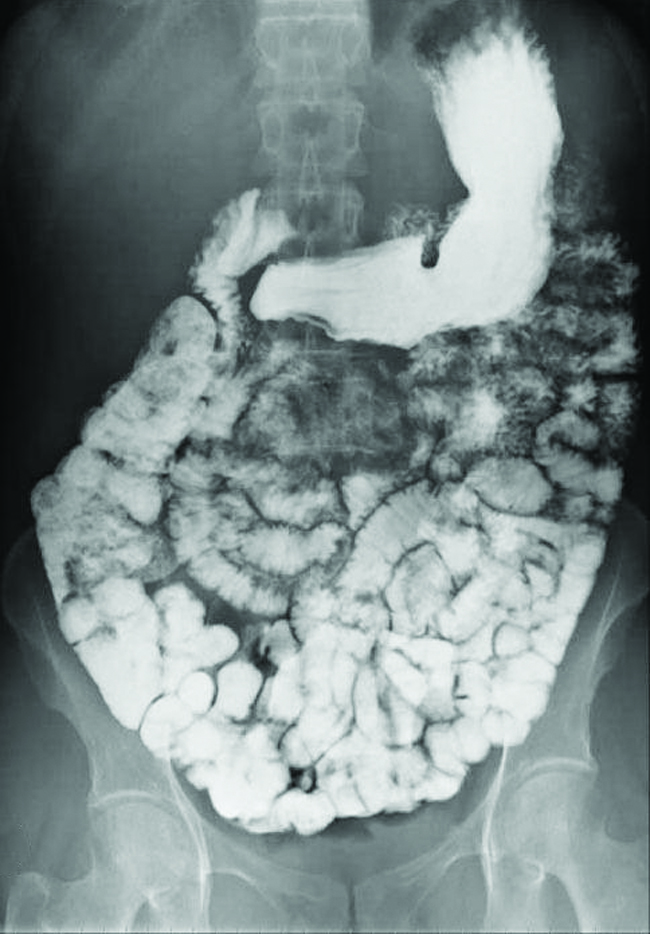

Various types of medical imaging techniques are used to aid diagnoses of illnesses in a noninvasive manner. One such technique utilizes the ingestion of a barium compound before taking an X-ray image. A suspension of barium sulfate, a chalky powder, is ingested by the patient. Since the Ksp of barium sulfate is 1.1 \(×\) 10–10, very little of it dissolves as it coats the lining of the patient’s intestinal tract. Barium-coated areas of the digestive tract then appear on an X-ray as white, allowing for greater visual detail than a traditional X-ray (see the figure below).

This figure contains one image. A black and white abdominal x-ray image is shown in which the intestinal tract of a person is clearly visible in white.

The suspension of barium sulfate coats the intestinal tract, which allows for greater visual detail than a traditional X-ray. (credit modification of work by “glitzy queen00”/Wikimedia Commons)

Further diagnostic testing can be done using barium sulfate and fluoroscopy. In fluoroscopy, a continuous X-ray is passed through the body so the doctor can monitor, on a TV or computer screen, the barium sulfate’s movement as it passes through the digestive tract. Medical imaging using barium sulfate can be used to diagnose acid reflux disease, Crohn’s disease, and ulcers in addition to other conditions.